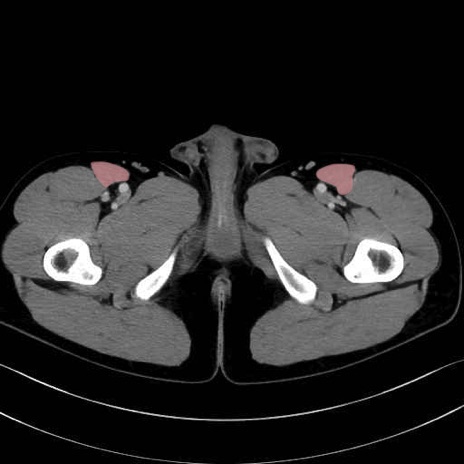

縫工筋(sartorius muscle) のCT画像の解剖

3. 殿部の筋肉(表層・中層・深層)

大殿筋 (Gluteus maximus)

中殿筋 (Gluteus medius)

小殿筋 (Gluteus minimus)

大腿筋膜張筋 (Tensor fasciae latae)

5. 大腿前面(大腿四頭筋群・伸筋群)

縫工筋 (Sartorius)